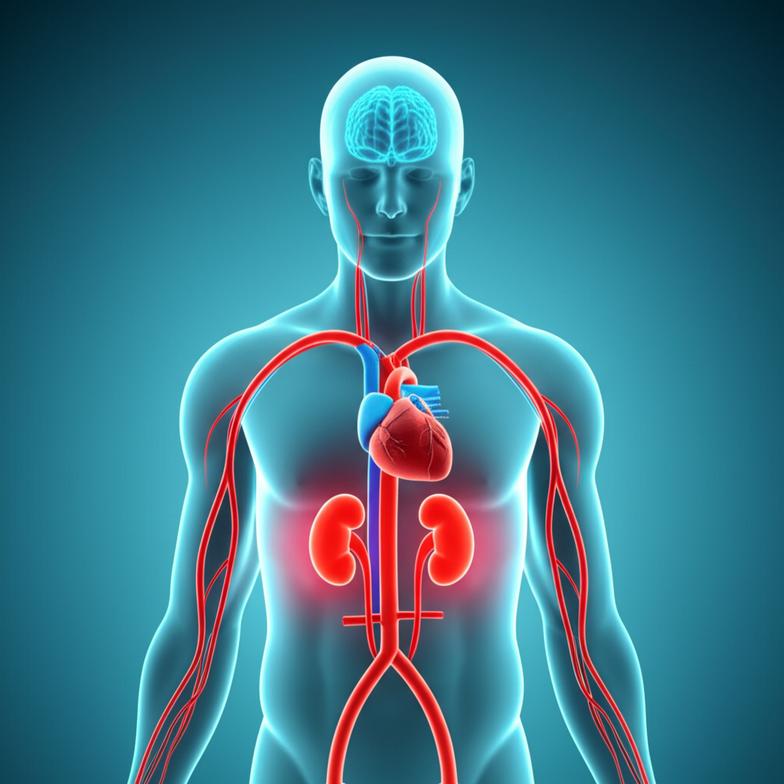

- ภาวะอักเสบเรื้อรัง (Chronic Inflammation): เมื่อน้ำตาลในเลือดสูง เซลล์จะตอบสนองด้วยการกระตุ้นระบบภูมิคุ้มกัน ทำให้เกิดการอักเสบทั่วร่างกาย ซึ่งเป็นรากฐานของโรคเรื้อรังหลายชนิด รวมถึงภาวะแทรกซ้อนของเบาหวาน เช่น โรคหัวใจและหลอดเลือด หรือความเสียหายของไต

- กระบวนการไกลเคชั่น (Glycation) หรือการเกิด AGEs: น้ำตาลส่วนเกินจะเข้าจับกับโปรตีนและไขมันในร่างกาย ก่อให้เกิดสารประกอบที่เรียกว่า Advanced Glycation End-products (AGEs) ซึ่งเป็นตัวการสำคัญที่ทำให้หลอดเลือดแข็งตัว เกิดริ้วรอยก่อนวัย ผิวหนังเสื่อมสภาพ และยังเป็นปัจจัยเร่งให้เกิดภาวะแทรกซ้อนที่ตา ไต และระบบประสาทอีกด้วย

- บวมตามร่างกาย ปัสสาวะเป็นฟอง หรือเหนื่อยง่ายผิดปกติ: อาจเป็นสัญญาณของภาวะไตเสื่อมจากเบาหวาน (Diabetic Nephropathy) ที่เกิดจากความเสียหายของหลอดเลือดฝอยในไต